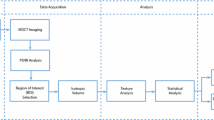

Texture analysis is an image processing method that aims to assess the distribution of gray-level intensity and spatial organization of the pixels in the image. The purpose of this study was to investigate whether the texture analysis applied to cone beam computed tomography (CBCT) images could detect variation in the condyle trabecular bone of individuals from different age groups and genders.

The sample consisted of imaging exams from 63 individuals divided into three groups according to age groups of 03–13, 14–24 and 25–34. For texture analysis, the MaZda® software was used to extract the following parameters: second angular momentum, contrast, correlation, sum of squares, inverse difference moment, sum entropy and entropy. Statistical analysis was performed using Mann–Whitney test for gender and Kruskal–Wallis test for age (P = 5%).